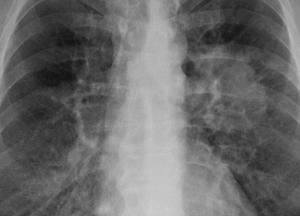

По данным Всемирной организации здравоохранения, в 2020 году на долю онкологических заболеваний пришлось около 10 млн смертей. Смертность от онкологических заболеваний в Украине в 2 раза выше, чем в Европе, при этом детская смертность превышает таковую в Европе в 2,5 раза. Самыми распространенными (с точки зрения новых случаев) были рак груди, рак легких, толстой и прямой кишки, простаты, кожи и желудка. При этом больше всего смертей в 2020-м было зафиксировано в результате заболевания раком легких.

Болезнь начиналась с затяжного кашля у 75% больных раком легких. Медики призывают быть внимательными к своему здоровью и, если кашель не проходит за 2-3 недели, немедленно обратиться в больницу для исследований и постановки точного диагноза.

Кроме того опасным симптомом медики назвали частые боли в области груди, которые сопровождаются одышкой.

Часто возникающие бронхит или пневмония, также должны насторожить.

Немаловажным симптомом выступает кровь в мокроте, она присутствует у 25-50% случаев выявления рака легких.

Данный вид онкологии имеет свои факторы риска развития и на первом месте стоит курение. Несмотря на это, последние данные говорят, что 25% пациентов с таким диагнозом вообще никогда не имели подобной вредной привычки. Спровоцировать рак легких может вирус Эпштейн-Барр, папилломы человека, гепатиты В и С, туберкулез, а также загрязнение окружающей среды.